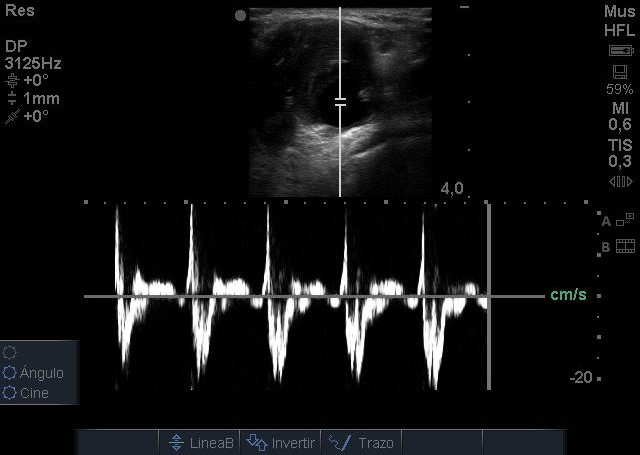

Se visualiza aneurisma de 2 centímetros con imagen compatible con trombo intramural. En modo Doppler flujo turbulento. Realizamos ecografía de rodilla contralateral y aórtica sin hallazgos reseñables.

Juicio Clínico: Aneurisma poplíteo con trombo intramural.